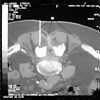

wird ein Querschnitt durch das betroffenen LWS-Segment erstellt (Abb.2).

| Abb.

2 |